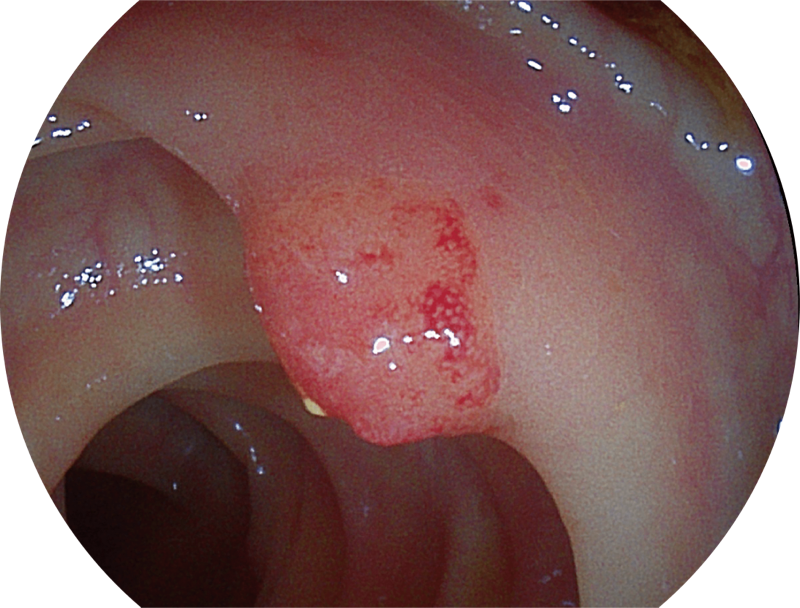

聚谱成像

(Spectral Focused lmaging, SFI)

能够凸显黏膜浅层和中层血管轮廓,适用于中、远景观察下的病灶识别和早癌筛查。